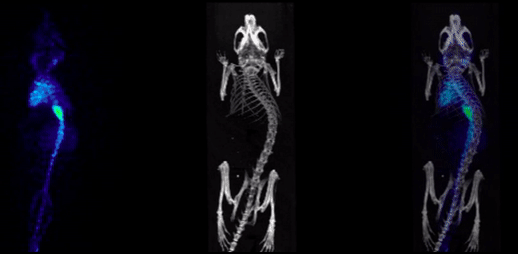

2、和SPECT組合的CT成像

SPECT/CT組合圖像,小鼠的骨骼成像:99mTc-HDP,94.35MBq (2.55mCi) @ start acquisition,采集時(shí)間60min。

和SPECT融合.png

3、和光學(xué)成像組合的CT成像

CT圖像可以和小動(dòng)物活體光學(xué)圖像融合,用于結(jié)構(gòu)性成像,輔助定位。

圖14. CT和光學(xué)融合圖.png